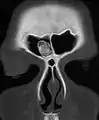

Osteoma of the frontal sinus seen on x-ray